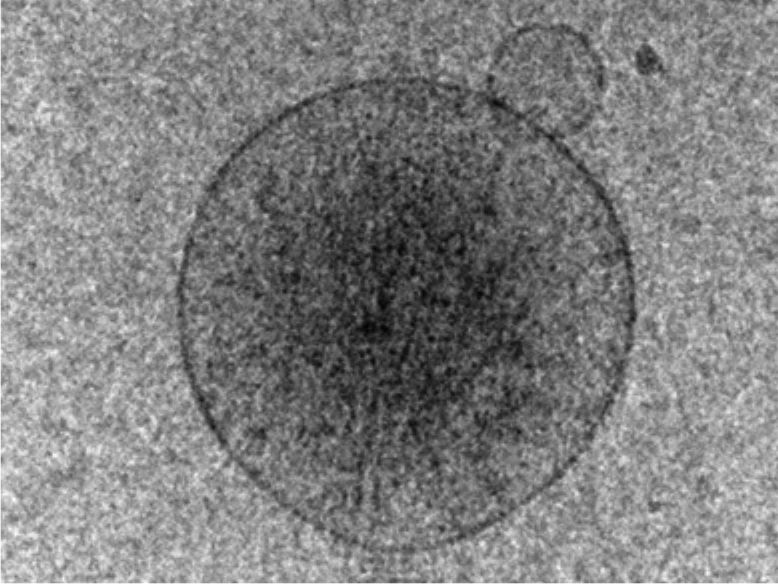

Viktoria Weber: Extrazelluläre Vesikel, kurz EVs, sind von der Form her kleine Bläschen in einem Größenbereich von etwa 30 bis 1.000 Nanometer, die von einer Membrandoppelschicht umgeben sind. Sie finden sich in allen Körperflüssigkeiten, vom Blut bis zur Tränenflüssigkeit. Zellen, setzen die Vesikel sowohl unter physiologischen als auch unter pathologischen Bedingungen frei, geben sie also aktiv ab. EVs erfüllen verschiedene Funktionen, die nach und nach entdeckt und verstanden wurden, etwa bei der Signalübertragung von Zelle zu Zelle oder bei der Regulation des Immunsystems. Das macht sie für die Forschung interessant.

Weber: Nur mit entsprechender Geräteausstattung, wie sie uns in der Core Facility am Campus Krems zur Verfügung steht, ist die Charakterisierung von EVs möglich. Mittels Durchflusszytometrie können wir Vesikel direkt in ihrer Umgebung, in unserem Fall in Blut, charakterisieren, d.h., Verfälschungen der Ergebnisse durch Anreicherungsprozesse werden weitestgehend vermieden. Allerdings können wir mit dieser Methode nur einen bestimmten Größenbereich erfassen, die ganz kleinen Vesikel „sehen“ wir damit nicht – oder noch nicht, denn die technischen Möglichkeiten verbessern sich laufend. Zusätzlich ermöglichen bestehende Kooperationen mit der Medizinischen Universität Wien eine weitere Charakterisierung, z.B. mittels Imaging Flow Cytometry. Die Kombination von Durchflusszytometrie mit Fluoreszenzmikroskopie ermöglicht dabei, von jedem Vesikel ein Bild zu generieren. So konnten wir zeigen, wie Vesikel von Blutplättchen mit Immunzellen interagieren.